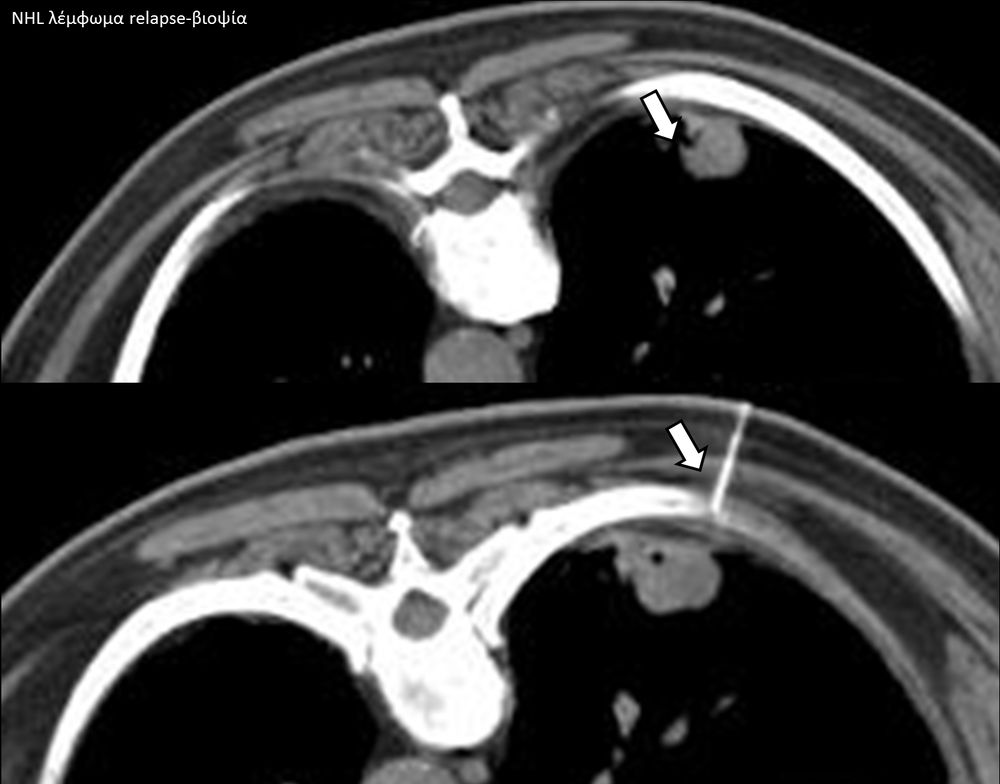

Η διαδερμική βιοψία είναι μία ελάχιστα επεμβατική μέθοδος λήψης υλικού από τον όγκο για κυτταρολογική και ιστολογική εξέταση, από εστιακές αλλοιώσεις του ήπατος, πνεύμονα, νεφρού κλπ. Συστήνεται από τον κλινικό ιατρό ανάλογα με το είδος και το μέγεθος της βλάβης και πραγματοποιείται με ασφάλεια από επεμβατικό ακτινολόγο με την καθοδήγηση αξονικού τομογράφου ή υπερήχων. Στη σύγχρονη ογκολογική θεραπεία όπου γίνεται προσπάθεια καταπολέμησης του καρκίνου σε μοριακό επίπεδο κρίνεται αναγκαία η ακριβής ιστολογική ταυτοποίηση του όγκου ώστε να εφαρμοσθεί εξατομικευμένη θεραπεία για το βέλτιστο αποτέλεσμα. Οι κατευθυνόμενες βιοψίες στοχευουν στο να παρέχουν στον κλινικό ογκολόγο το απαραίτο ιστοπαθολογικό υλικό που θα του επιτρέψει να εφαρμόσει την κατάλληλη θεραπεία για τον ογκολογικό ασθενή.